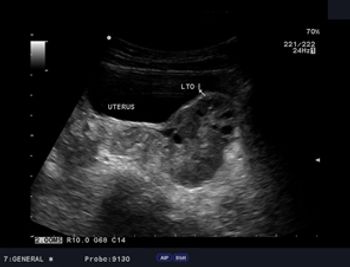

What is your diagnosis in this 7-year-old girl who presented with left pelvic pain?